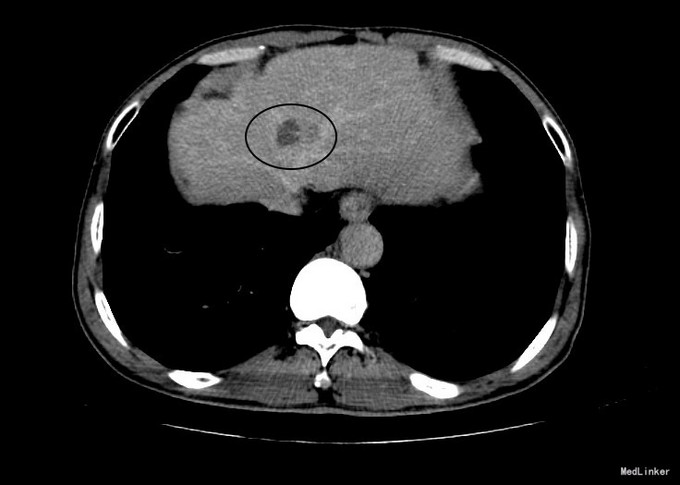

诊断:乙肝肝硬化 代偿期 静止性(C-P A级);2、原发性肝癌局部消融术后。 治疗:患者入院后护肝治疗,查CT发现提示肝S4段可见一结节状稍低密度影,边界模糊,其内见斑点状高密度影,范围约2.52*2.0cm,增强扫描该病灶边缘呈结节样强化,延迟期密度低于周围肝实质,考虑肝癌局部复发,行经皮超声引导射频消融治疗。为确诊肝癌,术前超声造影,CEUS:动脉期治疗后病灶边缘见结节样强化。

患者CECT及CEUS均提示肝癌复发,复发病灶超声显示清晰,无肝穿活检及射频消融绝对禁忌症,行射频消融治疗术后恢复良好。化验:血细胞分析(五分类):白细胞计数 9.8 10^9/L、血小板计数 172.0 10^9/L、血红蛋白 143 g/L、中性粒细胞百分比 63.0 %,肝功酶谱:丙氨酸氨基转移酶 80 U/L、总蛋白 69.0 g/L、白蛋白 35.8 g/L、总胆红素 23.7 umol/L,甲胎蛋白测定:甲胎蛋白(AFP) 11.54 ng/mL。复查MR平扫,MR提示消融部位良好,消融范围充分。患者术后一周病情稳定,未见射频穿刺相关并发症,化验肝功改变与肝组织被消融密切相关,加用异甘草酸镁加强降酶护肝治疗,术后一周出院